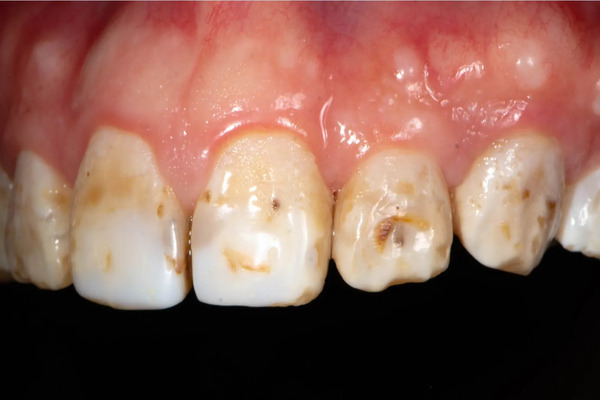

Răng đổi màu: vàng, nâu, xỉn, mất độ bóng

Thay đổi màu răng là dấu hiệu dễ thấy khi men răng bị tổn thương hoặc mòn mỏng. Răng có thể ngả vàng, nâu hoặc xỉn màu do mất khoáng, mảng bám tích tụ hoặc các vết ố lâu ngày. Khi men răng mất độ bóng tự nhiên, lớp ngà bên trong lộ ra nhiều hơn, làm răng trông kém thẩm mỹ và khiến người bệnh mất tự tin.

Tình trạng đổi màu này còn liên quan đến thói quen ăn uống, hút thuốc hoặc vệ sinh răng miệng chưa đúng cách. Việc điều trị sớm như tẩy trắng răng, lấy cao răng hoặc phục hình sứ có thể giúp cải thiện đáng kể, phục hồi lại sự sáng đẹp và bảo vệ răng tốt hơn trong thời gian dài.

Xuất hiện vệt trắng đục hoặc mảng mờ trên bề mặt răng

Các vết trắng đục hoặc mảng mờ trên răng thường xuất hiện khi men răng bắt đầu mất khoáng nhẹ. Lúc này, răng chưa bị sâu nhưng bề mặt trông kém tự nhiên và không đều. Đây là dấu hiệu cảnh báo sớm cho thấy men răng đang yếu dần và cần được chú ý để tránh tổn thương nặng hơn.

Răng dễ bị sâu hơn bình thường

Sâu răng xảy ra khi men răng yếu đi và không còn đủ khả năng chống lại vi khuẩn và axit trong miệng. Khi lớp bảo vệ này suy giảm, vi khuẩn dễ dàng tấn công và phá hủy cấu trúc răng. Thói quen ăn uống nhiều đường, vệ sinh răng không đúng cách cũng làm mảng bám tích tụ, khiến nguy cơ sâu răng tăng cao. Nếu không xử lý sớm, sâu răng có thể gây đau nhức, viêm nướu và thậm chí phải nhổ bỏ răng.

Sâu răng và cao răng là hai yếu tố gây hại trực tiếp cho men răng. Sâu răng hình thành khi vi khuẩn và mảng bám tích tụ lâu ngày, phá vỡ khoáng chất của men và tạo ra các lỗ nhỏ gây đau, ê buốt. Trong khi đó, cao răng là mảng bám đã cứng lại, chứa nhiều vi khuẩn, khiến men răng dễ bị mẻ, đổi màu hoặc xuất hiện các vệt trắng đục.